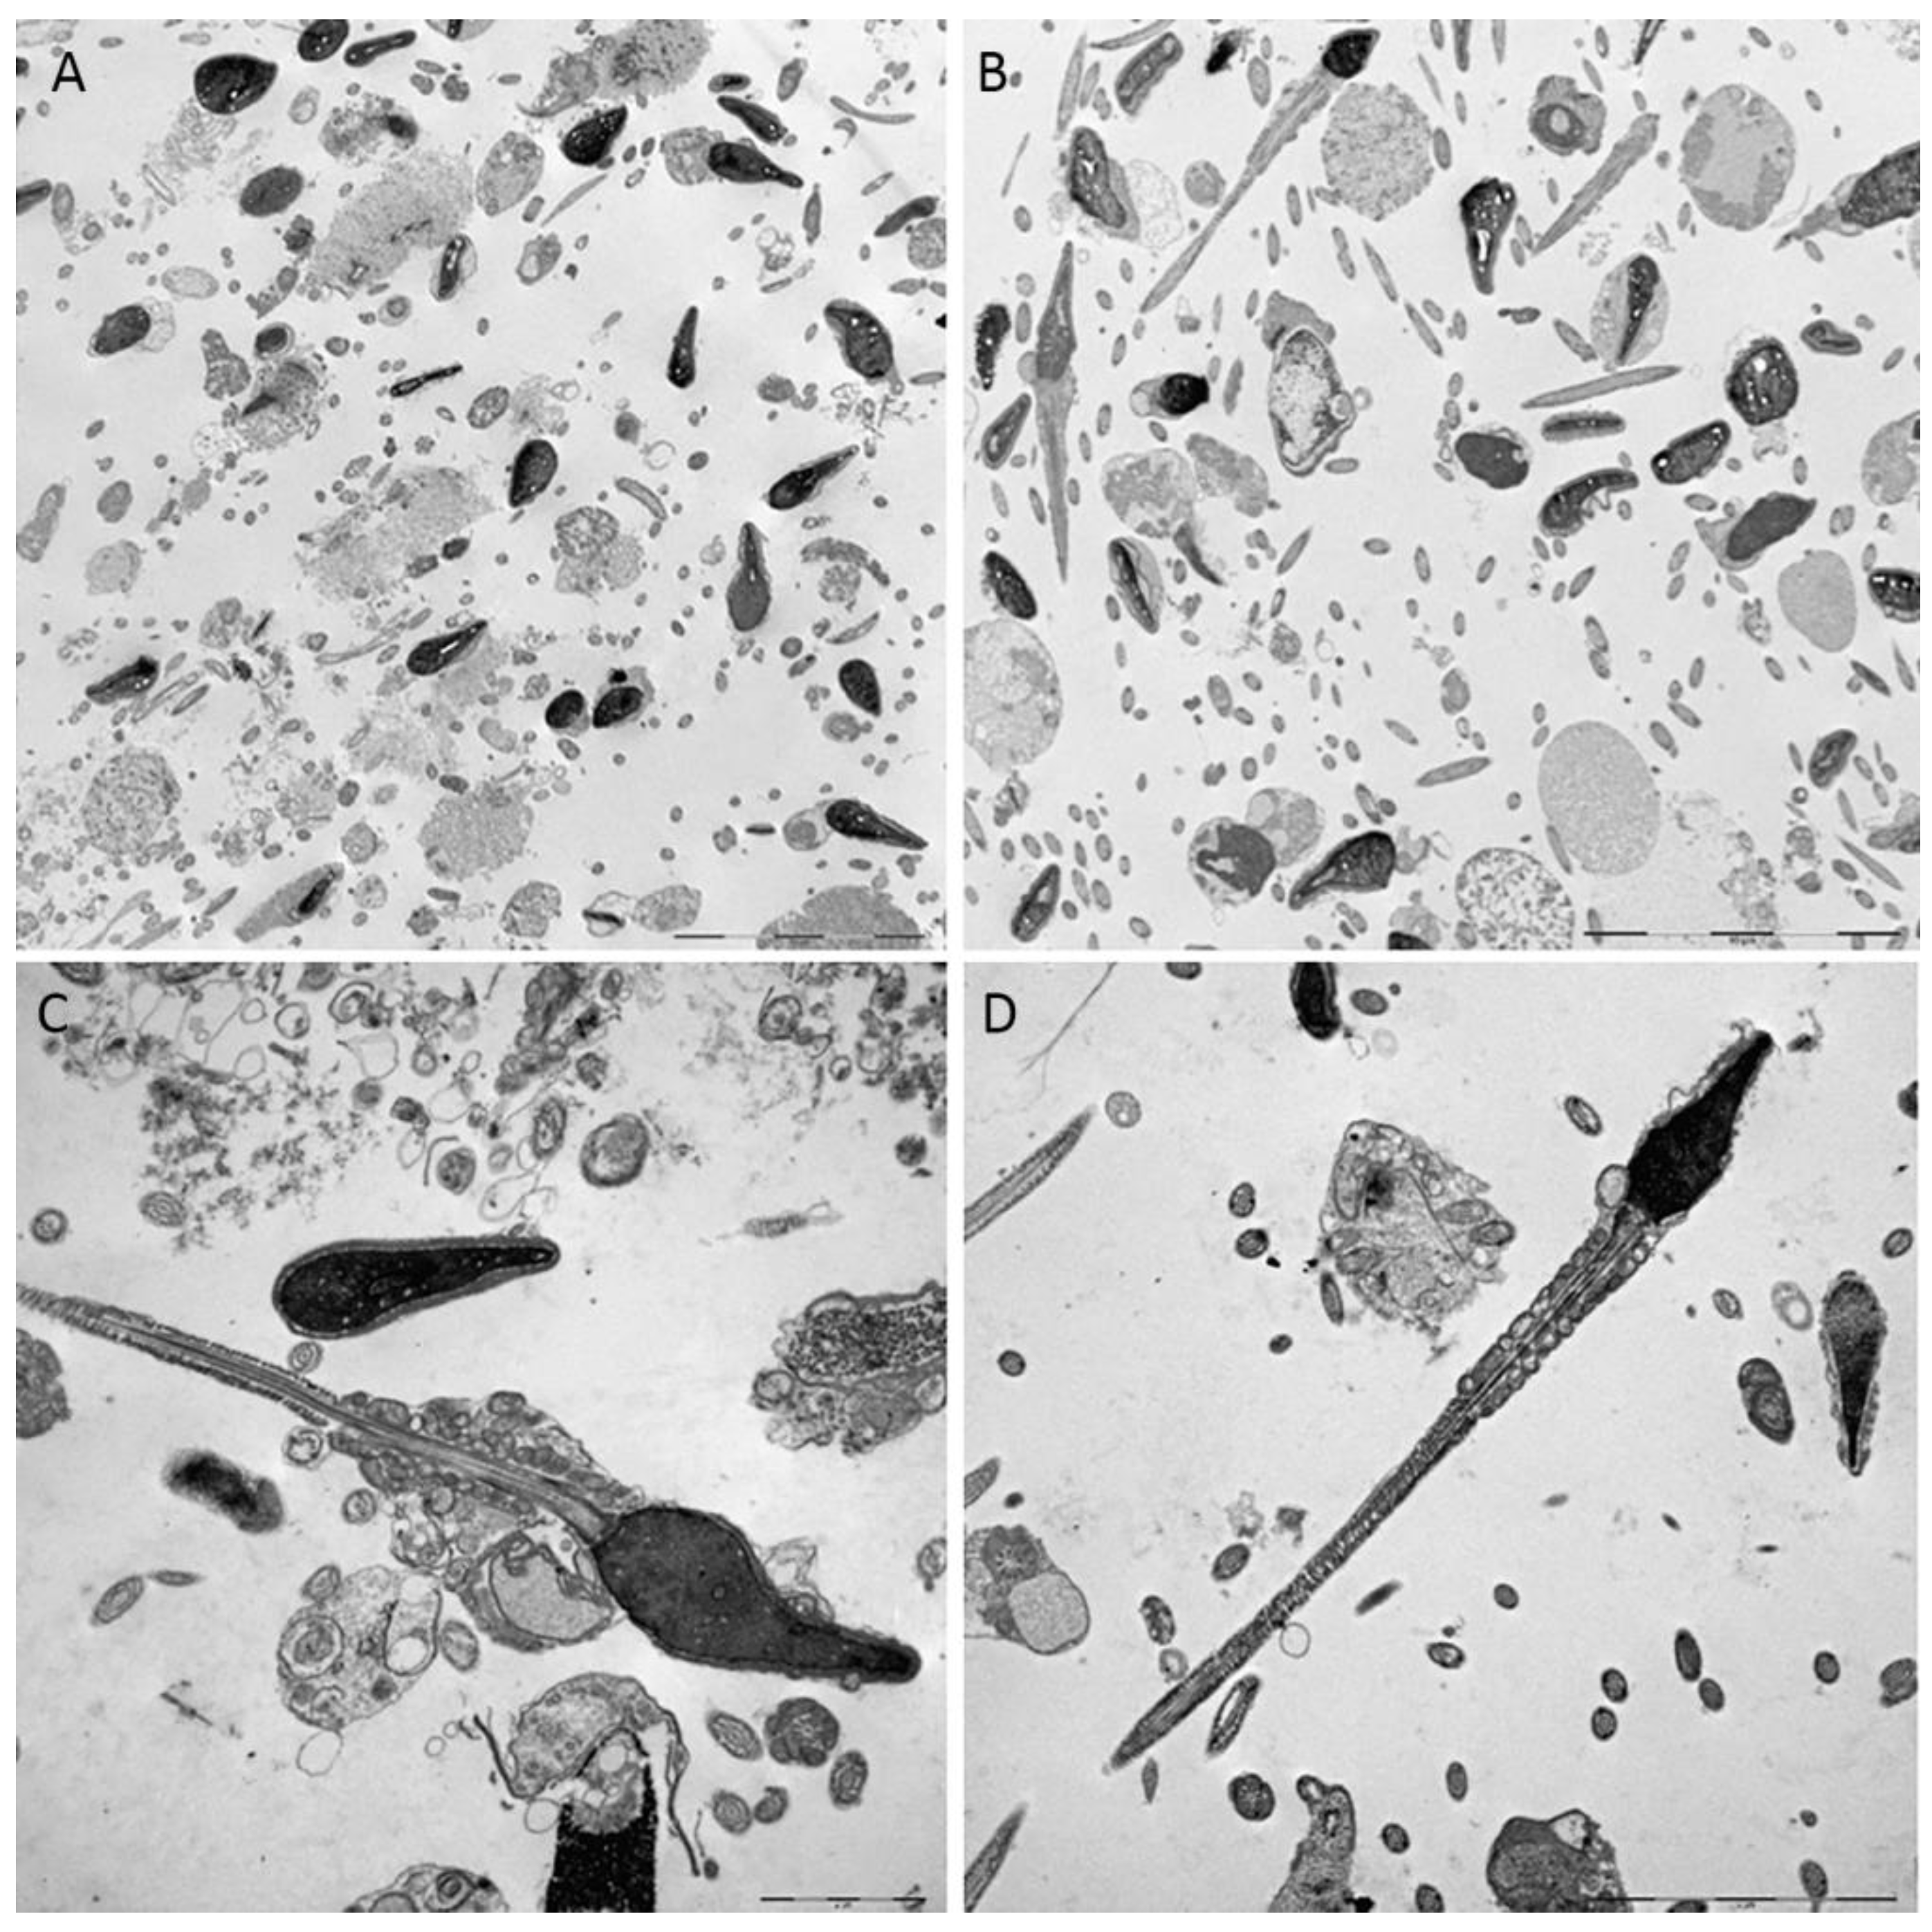

3.3. TEM Evaluation of Untreated and Treated Sample with Myo-inositol